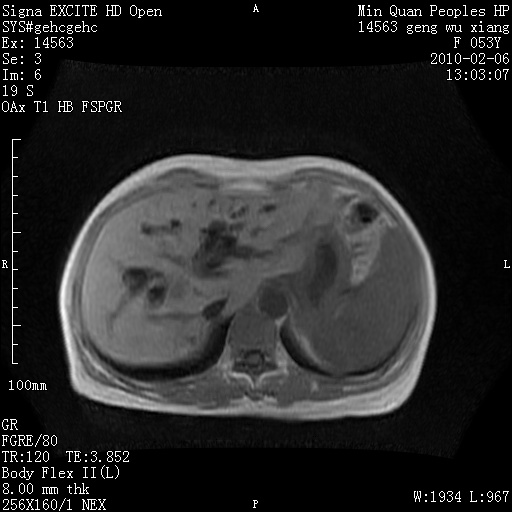

标题: MRI2762:胆道梗阻原因?

f,53y,全身黄染多日。

高位胆道梗阻 胆管癌可能性大

支持 高位胆道梗阻 胆管癌可能性大。